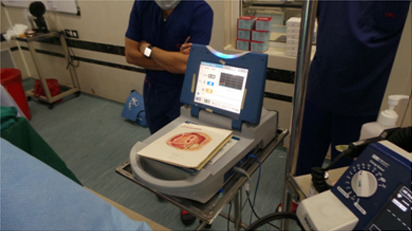

Application of Abalation around Pulmonary Veins

Cardioblate Diathermy For Intra- Atrial Abalation